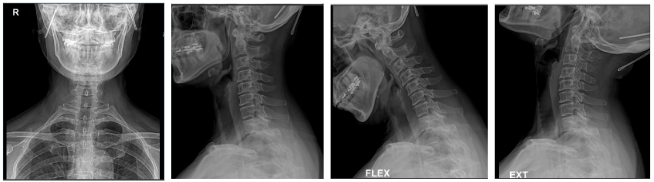

경추부 방사선촬영 상에서는 측만과 전만소견 그리고 추간판의 간격이 좁아진 소견을 보였으며, 경추 MRI 검사상 목디스크 소견을 보였습니다. 손저림 때문에 뉴론틴이라는 약을 2달정도 복용을 하고 있었으나 별 효과는 없었습니다.